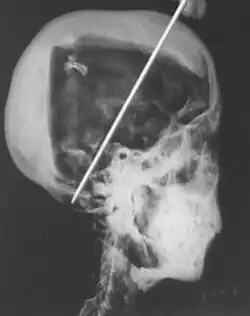

X-ray of Tutankhamun's head showing two levels of resin inside the skull

In 1968 R. G. Harrison, a professor of anatomy, used a portable X-ray machine to re-examine the mummy of Tutankhamun. Harrison quickly discovered that Carter had dismembered the mummy, something that is not mentioned in his publication but visible in photographs of the unwrapping. The mummy, surrounded by cotton wool and secured by modern bandages, had deteriorated since last photographed by Carter's team in 1926. The beaded skull-cap had disappeared, as had most of the skin on the head. The eyes appeared to be wide open as the eyelids had been destroyed, and the ears were broken off. The ribs had been sawn off and the front of the king's chest, including sternum and clavicles, had been removed. Stray beads from the large beaded collar were seen scattered in the torso on the X-rays. The limbs had been moved and further disarticulated, with the left hand and thumb of the right hand found in the sand under the body, and some of the digits on the hands and feet missing.[80][58][81] Although not mentioned by Harrison, the king's penis was also missing.[81] The additional damage to the mummy and the removal of the skullcap and collar likely occurred during the Second World War,[58] and components suggested to be from the collar have since appeared on the antiquities market.[82]

The X-rays revealed two levels of resin inside the skull. One was introduced when the body was lying on its back, pooling at the back of the head; the other when the head was tilted far back, settling at the top of the skull. Also present in the skull cavity were small bone fragments which Harrison initially believed to be the result of the embalming process. The fact that skull fragments were discovered led many to assume the king was murdered by a blow to the head, but the X-ray could not support or discredit this theory. His age at death was again estimated to be around 18, with a projected height in life of 168.9 centimetres (5 ft 6.5 in).[80] Serological analysis undertaken by the same team determined that Tutankhamun and the KV55 mummy had the same blood group, further indicating a familial relationship.[83]